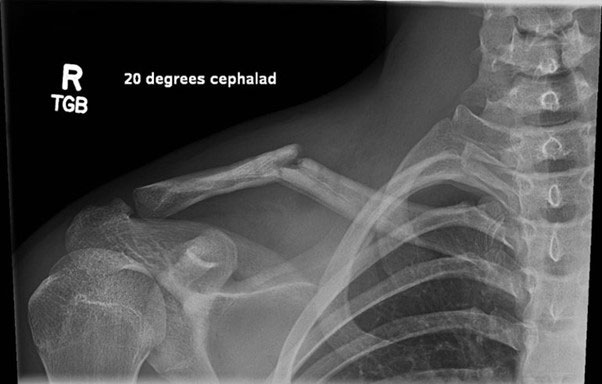

Once again, he was going well and back into his sport when again he fell – this time fracturing the distal end of the clavicle, just next to the plate that I had put in in July of the preceding year (see image 4 below).

Fracture of distal clavicle next to existing plate after fall from mountain bike